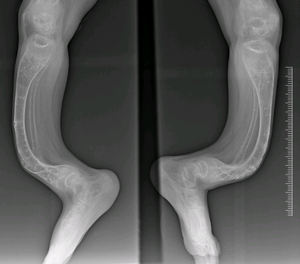

Can you hit the right diagnosis? Symptoms include: bone deformities.multiple broken bones.loose joints.weak teeth.blue sclera, or a bluish color in the white of the eye.bowed legs and arms.kyphosis, or an abnormal outward curve of the upper spine.scoliosis, or an abnormal lateral curve of the spine.

Rickets is a skeletal disorder that's caused by a lack of vitamin D, calcium, or phosphate.However, Osteogenesis imperfecta (OI) is a group of genetic disorders that mainly affect the bones. People with this condition have bones that break easily, often from mild trauma or with no apparent cause.